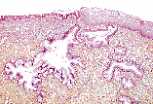

这是宫颈唇的大体镜下(CL)观察视图,可分辨出:

- 宫颈管黏膜;

- 宫颈阴道部黏膜;

- 肌层。

宫颈管黏膜的特征是具有大量皱襞,皱襞表面被覆单层柱状上皮,上皮向深部凹陷形成分支状的宫颈管腺隐窝。

该上皮由黏液分泌细胞(闭合型黏液细胞)和少量纤毛细胞组成,可在激素调控下产生宫颈黏液。

宫颈管与宫颈阴道部的上皮移行分界清晰。宫颈管的单层柱状上皮被宫颈阴道部的复层扁平上皮(鳞状上皮)取代。

宫颈阴道部的复层扁平上皮细胞因富含糖原而呈淡染状,其厚度与雌激素的作用程度成正比。

宫颈阴道部的鳞状上皮细胞从基底层到表层逐渐“成熟”并最终脱落。可分辨出:

- 深染的基底细胞;

- 旁基底细胞;

- 开始变扁平的中层细胞;

- 表层细胞;

- 固缩的表层细胞(核固缩表层细胞)。